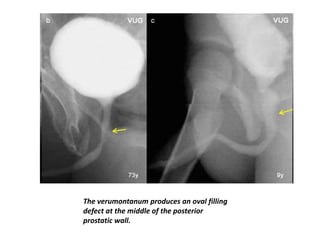

The verumontanum produces an oval filling

defect at the middle of the posterior

prostatic wall.